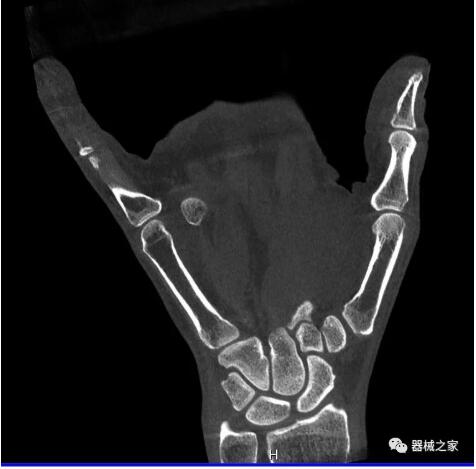

另外一款被稱為世界上最小的CT,它的重量僅300磅,不僅能夠掃查足部,還可以檢查膝蓋和上肢等。

與上面介紹的CT一樣,它同樣具有輻射低、占地空間?。?3*36)的特點(diǎn),隨開隨用(支持直接接入墻上的插座)。

這款CT使用非常方便,通過上下移動(dòng)保持與患者的手臂或者雙腿齊平,掃描快速,僅需要30秒左右就可以完成掃查。

以上介紹的CT均來自國外同一家公司,這些CT均配置了可視化軟件,可以進(jìn)行切片、3D重建以及大型CT附帶的所有典型的操作功能。

以下是這些“特立獨(dú)行”的CT所拍出來的圖像: